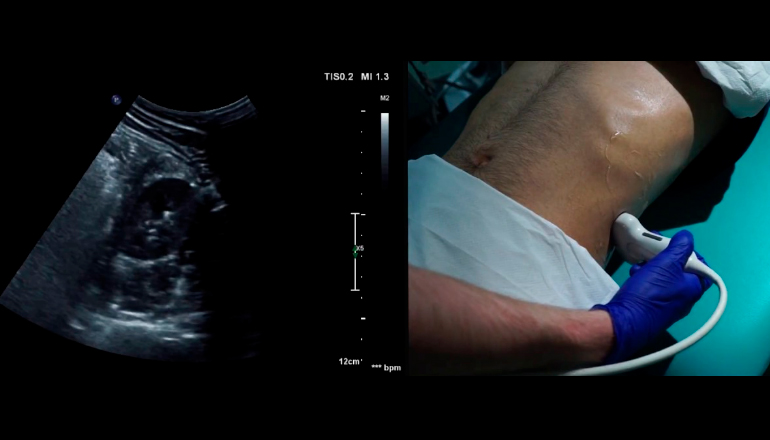

УЗИ выполняется с помощью портативного оборудования, не уступающего по точности стационарным аппаратам. Процедура аналогична проведению в клинике: